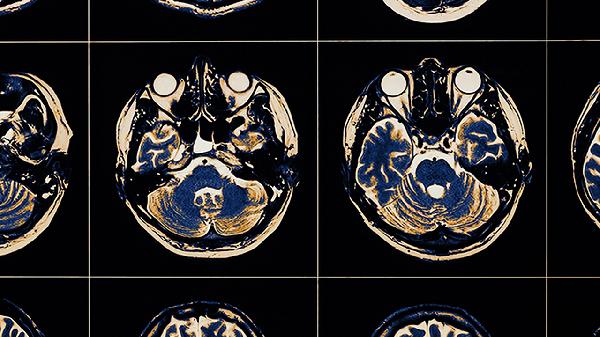

长期缺乏睡眠会影响前额叶皮层的功能,降低对默认模式网络的控制能力,让人更容易陷入无序的思绪中。每天睡眠时间少于六小时的人,出现思维碎片化的几率会增加三倍。保持规律的作息时间和睡前避免使用电子设备有助于改善睡眠质量。

长期处于高压状态下,会持续激活下丘脑-垂体-肾上腺轴,导致皮质醇升高,影响海马体和前额叶之间的协作。这时候大脑会不断重复处理压力相关的信息,形成思维反刍。定期进行有氧运动或腹式呼吸训练,有助于降低压力激素的水平。